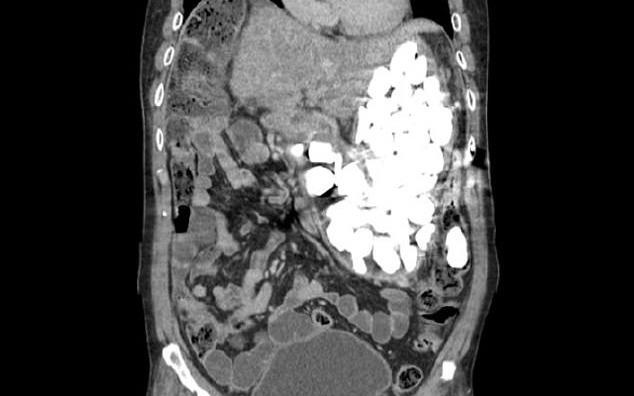

38 vật kim loại, hầu hết là chìa khóa, tiền xu và thẻ sim, được loại bỏ khỏi dạ dày bệnh nhân. Vật thể nhỏ nhất dài khoảng 2 cm. Các bác sĩ cũng tìm thấy một lưỡi mài bút chì và một nam châm hút hầu hết vật thể còn lại vào nó.

Ông Jayakumar mắc chứng rối loạn tâm thần và đã điều trị bệnh trong vòng 3 năm. Khi đang thực hiện thủ tục liên quan đến từ trường, một vấn đề kỹ thuật đã xảy ra. Bệnh nhân sau đó bị đau bụng dữ dội. Kết quả chụp CT vùng bụng cho thấy sự xuất hiện của rất nhiều vật kim loại trong bụng bệnh nhân.